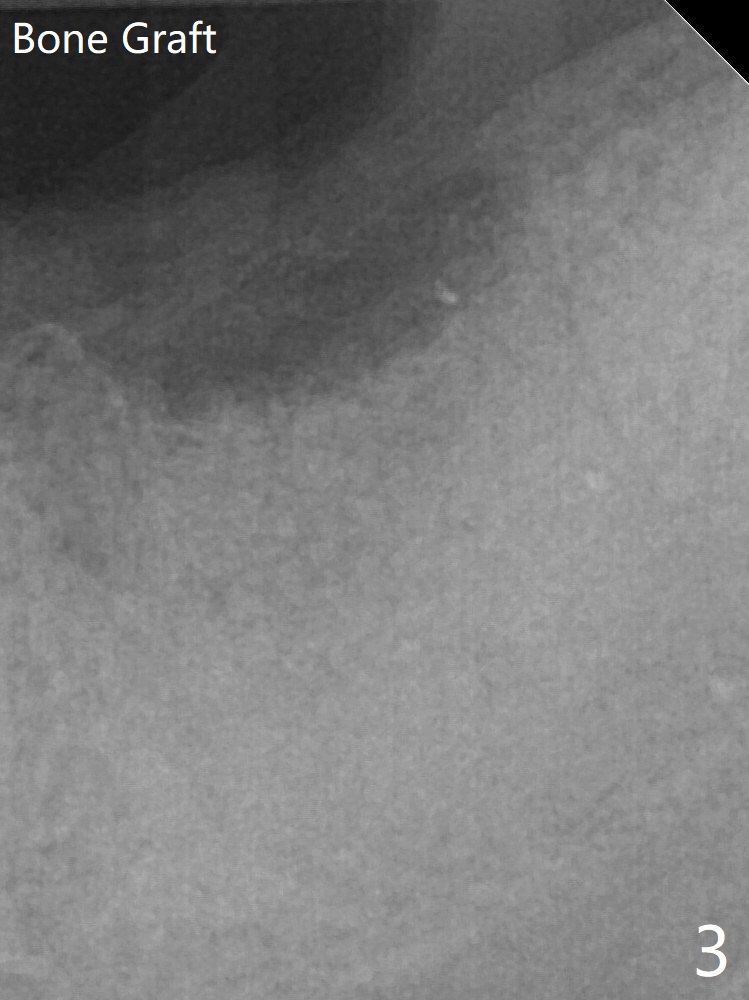

After extraction, a 7x11 mm tapered implant drops into the single socket, which is close to the Inferior Alveolar Canal (Fig.2). The bottom of the socket is sensitive to manipulation (explorer) after infiltration anesthesia. A 8x14 mm tapered tap is placed without binding, neither is a 8x14 mm cylindrical implant. The implant stability does not increase when Vera (.2-1.0 mm) or Vanilla (.5-1.0 mm) Graft is placed. Socket preservation is covered with Collagen plug and 6-month membrane (Fig.3). The patient returns for follow up 4 months postop; the bone graft appears to remain in the socket (Fig.7).